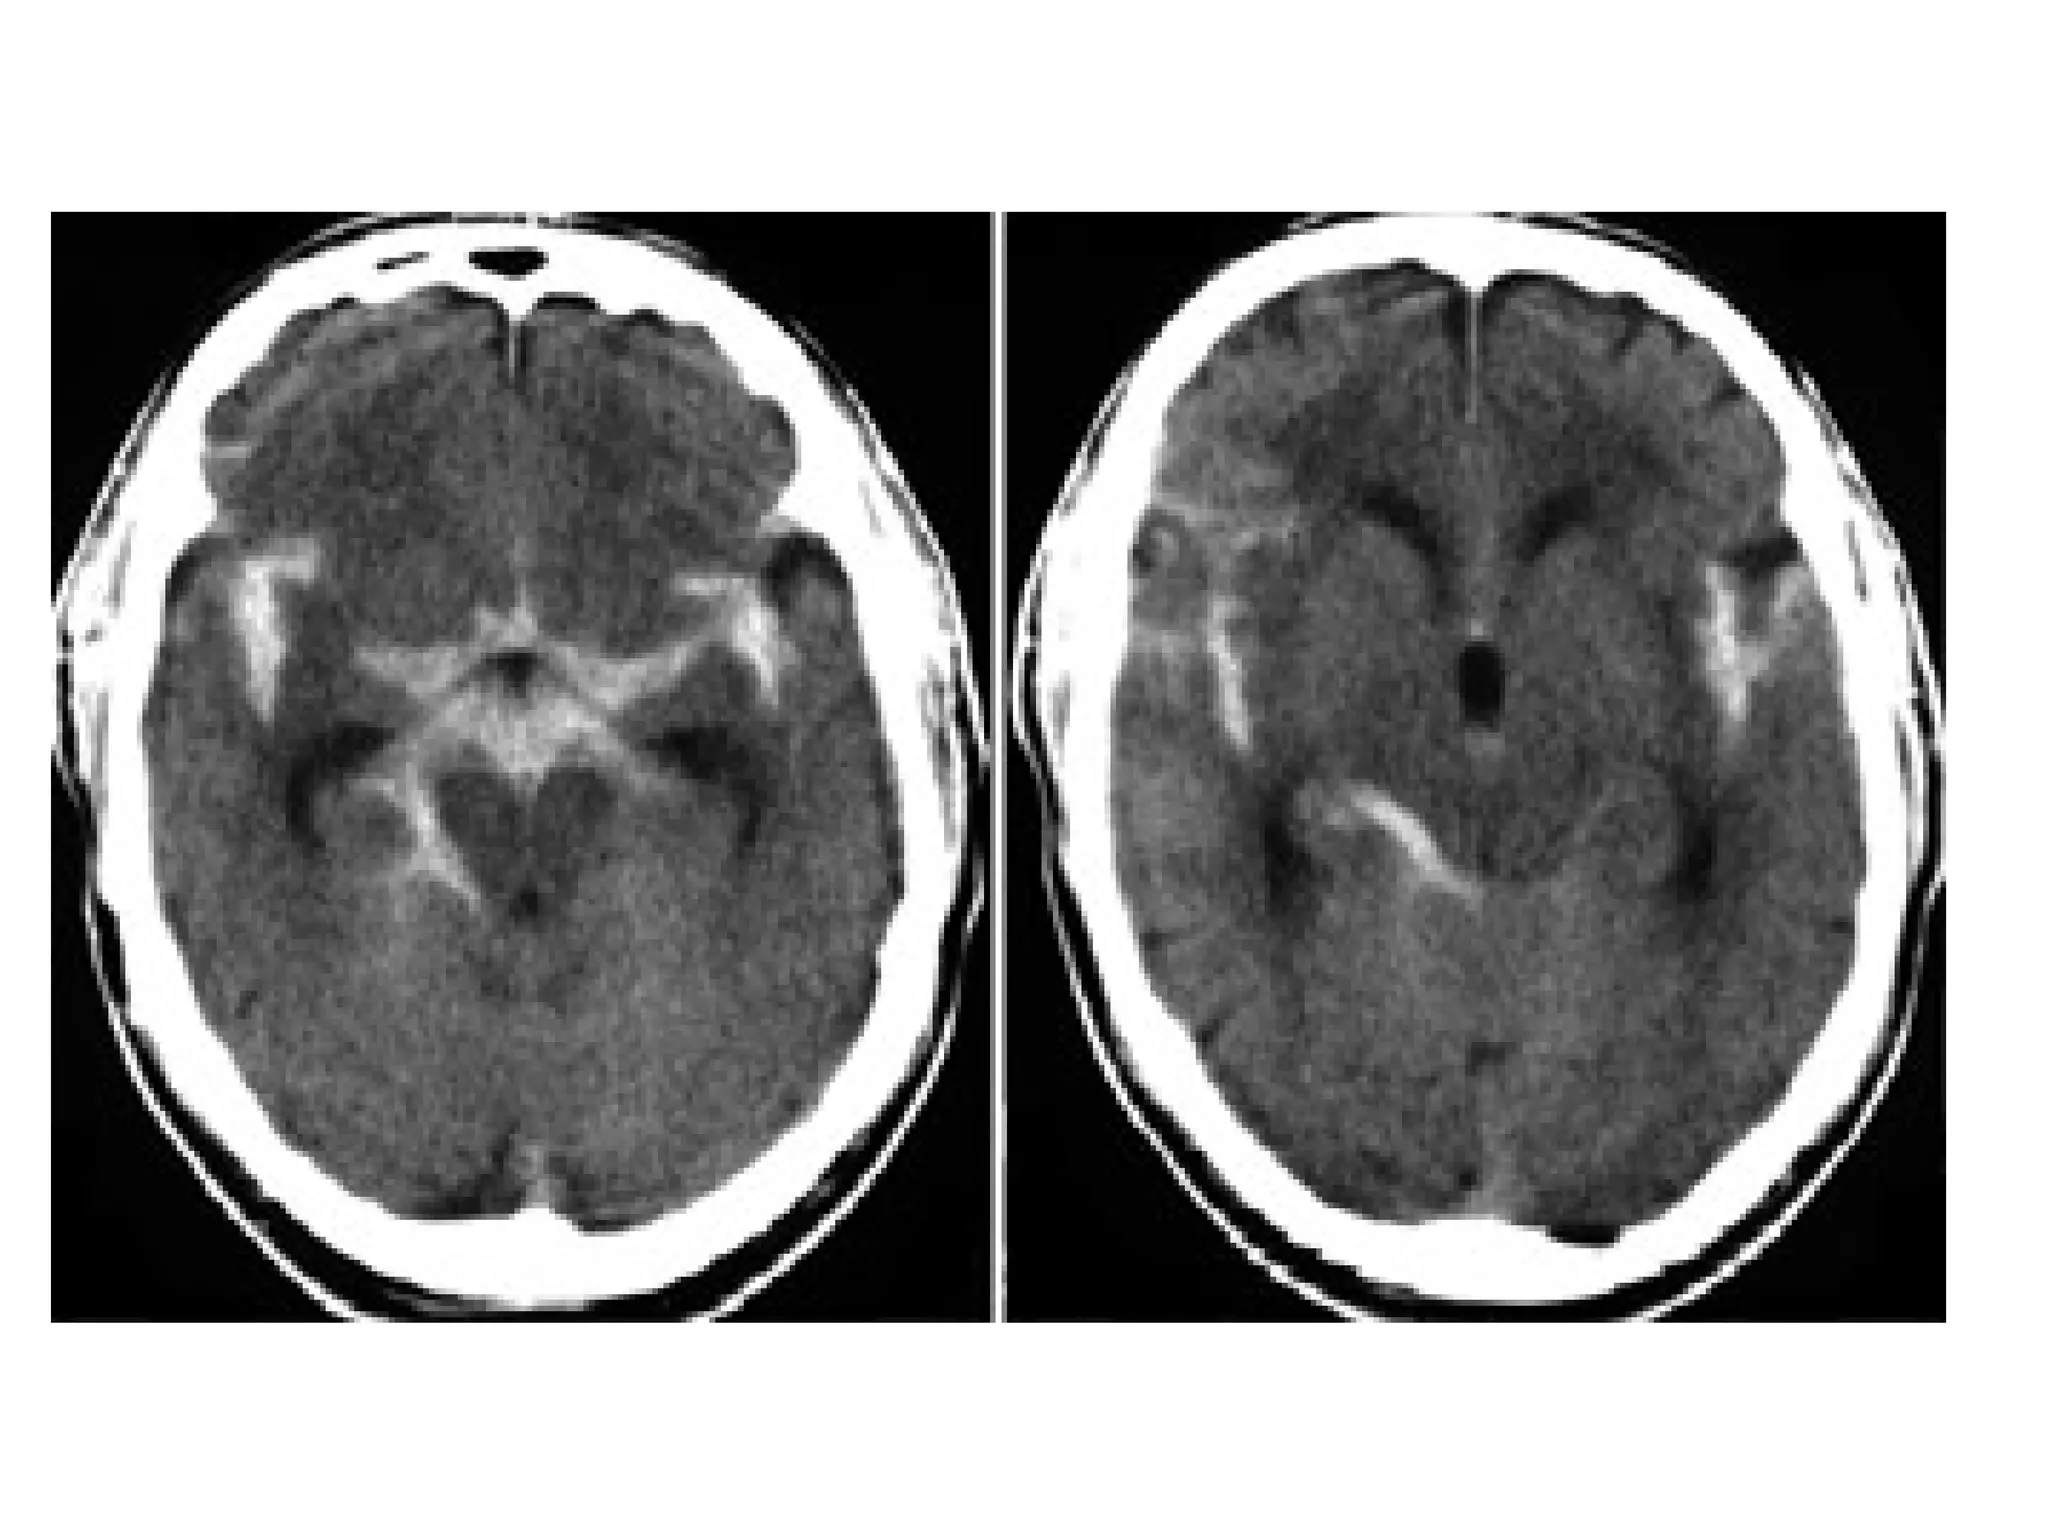

Patient with deep cerebral vein thrombosis , notice the bilateral infarctions in

the basal ganglia

The same patient , there is absence of flow void in the internal

cerebral veins, straight sinus and right transverse sinus (blue

arrows) , on the MRA the right transverse sinus is not visualized